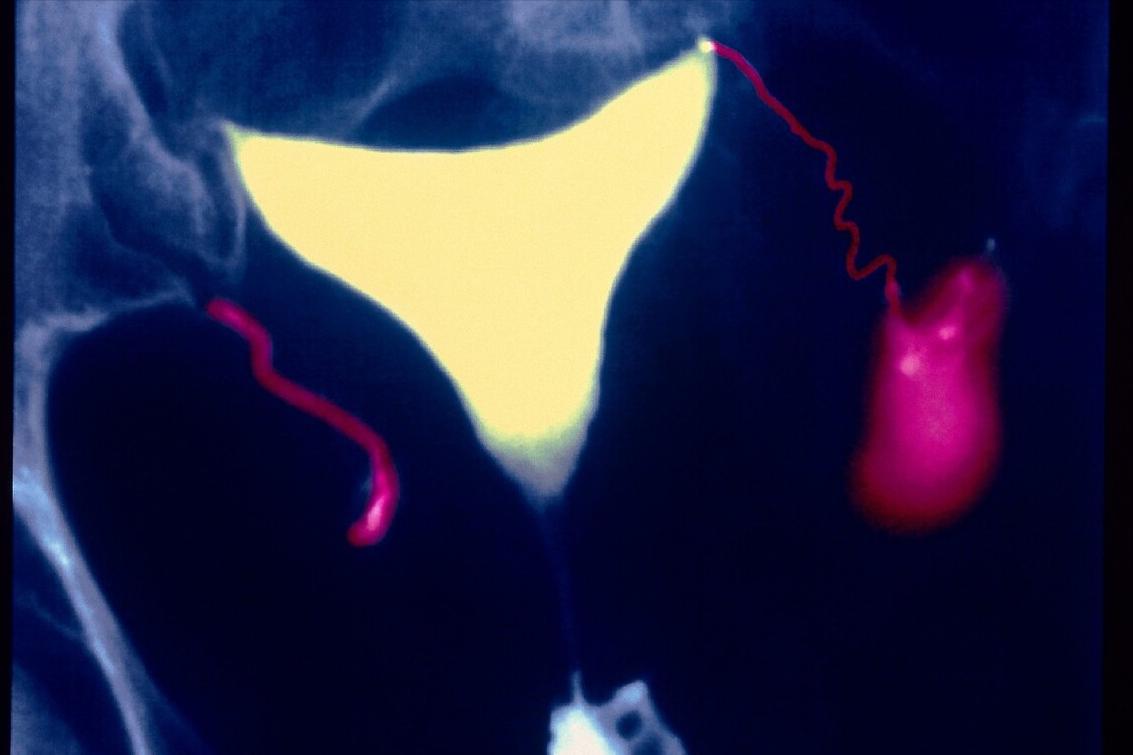

输卵管积水确实是困扰临床医生的令人头疼的问题。输卵管积水是引起不孕的主要原因之一,临床上非常常见,多见于反复人工流产、宫外孕、剖宫产术后,而积水的存在又降低试管婴儿的成功率,临床上处理非常棘手。

输卵管积水分两种类型:

对于这类病人,治疗原则就是果断进行腹腔镜下积水侧输卵管近端结扎+远端积水引流及伞端成型术。术后再进行胚胎移植,临床妊娠率大大提高。

当然,要警惕,有很多输卵管积水的患者,新鲜胚胎移植会发生宫外孕,原因不明。因此,对于输卵管积水不是很严重的患者,假如这个患者又不想做腹腔镜手术,可以采用全胚冷冻,进行冻胚周期移植,在移植前1-2天抽吸输卵管积水,还是有较高的临床妊娠率!当然,也要做好失败的心理准备,如果反复失败,还是建议做腹腔镜下输卵管结扎+积水伞端造口+积水引流术。